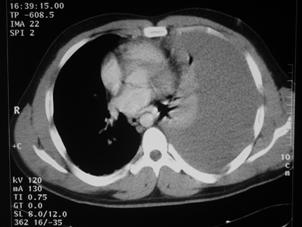

Leziune hepatica intraparenchimatoasa Leziune de lob drept

hepatic